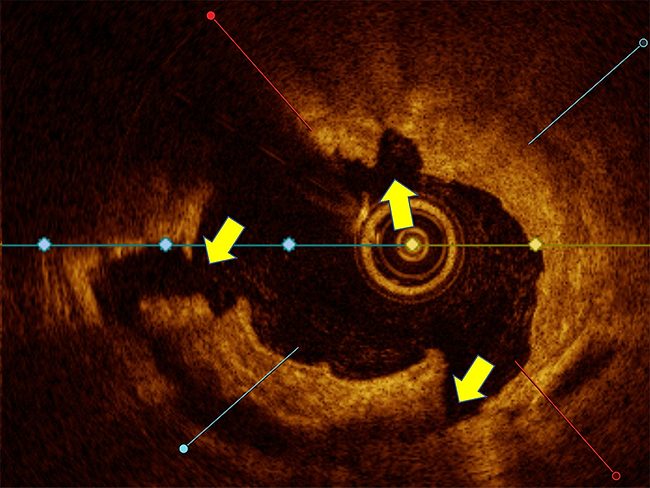

Heartflow CT scan predicts cardiac events 7 years out

Feb. 10, 2025

A 1,000-person study using Heartflow Inc. technology demonstrated that findings of coronary plaque on heart CT scans could indicate which patients were at risk of cardiovascular events up to seven years in the future – potentially providing a road map toward screening for heart disease, the leading cause of death for both men and women in the U.S. and worldwide.